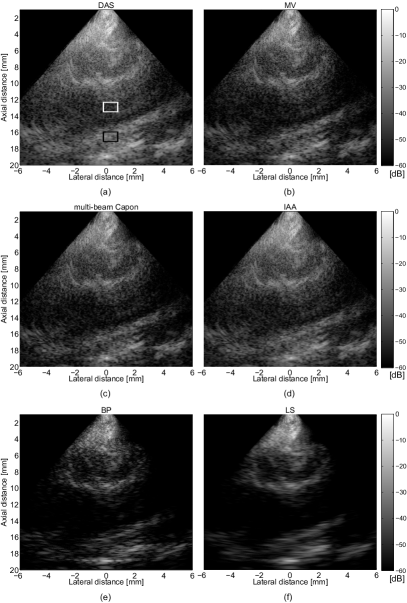

Refer to caption

Figure 3: (a) DAS, (b) MV, (c) multi-beam Capon, (d) IAA, (e) BP, and (f) LS BF results of the simulation of individual point scatterers.

With this simulation we evaluate the potential of the proposed methods in sparse mediums. The resulted beamformed images are illustrated in the Fig. 3. The result of DAS BF is shown in Fig. 3(a). Using the MV BF, the lateral resolution is improved compared with DAS, IAA, and LS BF (see Fig. 3(b)), and it is comparable with the result of multi-beam Capon BF, Fig. 3(c). Concerning the IAA beamformed result, as stated in [12], it gives better point-target resolvability than DAS, Fig. 3(d). The proposed BP BF have the best resolution of the point-like reflectors, being able to perfectly detect the 5 reflectors, by obtaining the most narrower mainlobes, due to the fact that BP results in a sparse representation of the beamformed signals, Fig. 3(e). As expected, LS beamformer results in solutions that tend to be smooth and regular, as in the Fig. 3(f).

Fig. 4 presents the lateral profiles of the compared BF methods at 65 mm. We can observe that multi-beam Capon and MV are comparable in terms of lateral profiles, but MV offers better delimitation of the two points. As observed, BP BF outperforms the other BF methods, being able to perfectly resolve the two points, suppressing also the sidelobes. Finally, LS BF gives the smoothest result.